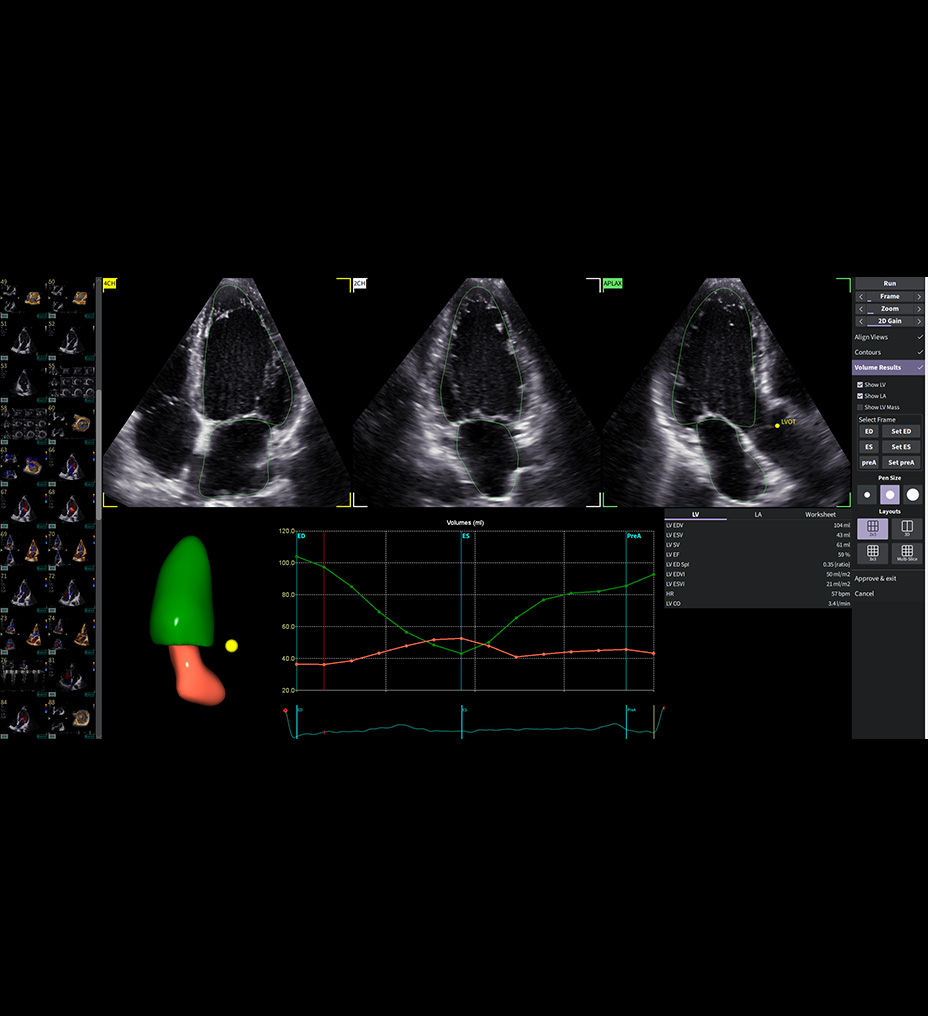

Conquer demanding workflows

Discover extraordinary performance and productivity

With outstanding image quality that sharpens borders, boosts clarity, and enhances definition between structures, Vivid Pioneer forms the foundation for AI-driven insights you can trust. Simplify and streamline measurements and quantification with automated tools, and rely on artificial intelligence that supports consistent, reliable results across users.